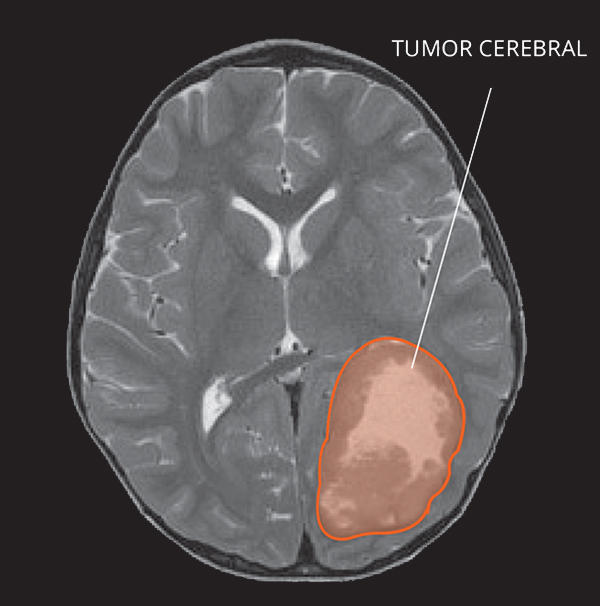

¿Cómo se ven los TNEP en las imágenes por resonancia magnética?

Los TNEP suelen aparecer al comienzo como una sola masa en la corteza cerebral (capa exterior del cerebro). Por lo general, los TNEP se ven brillantes con el uso de contraste y a veces se identifica más de un tumor. En ocasiones, se encuentran quistes o acumulaciones de líquido dentro de la masa tumoral. A veces también hay inflamación alrededor de los TNEP.